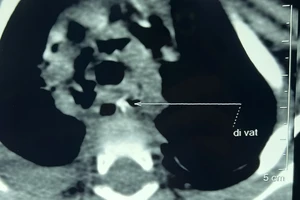

Bé 7 tháng tuổi hóc xương lươn gai sắc, tắc nghẽn phổi

19/05/2020 11:35